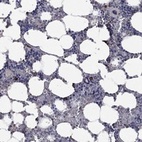

Immunohistochemical staining of human bone marrow shows strong cytoplasmic positivity in hematopoietic cells.